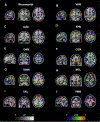

Resting state functional MR imaging methods can provide localization of the language system; however, presurgical functional localization of the language system with task-based functional MR imaging is the current standard of care before resection of brain tumors. These methods provide similar results and comparing them could be helpful for presurgical planning. We combine information from 3 data resources to provide quantitative information on the components of the language system. Tables and figures compare anatomic information, localization information from resting state fMR imaging, and activation patterns in different components of the language system expected from commonly used task fMR imaging experiments.